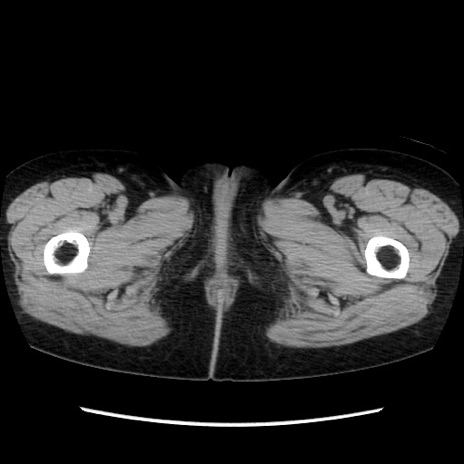

症例32(横断像)

【症例】40歳代 女性

【主訴】上腹部痛、嘔気・嘔吐

【現病歴】約9時間前頃から急に上腹部痛、嘔気、嘔吐が出現。改善しないため救急要請。

【既往歴】子宮頚癌(広汎子宮全摘術、放射線療法)、腸閉塞